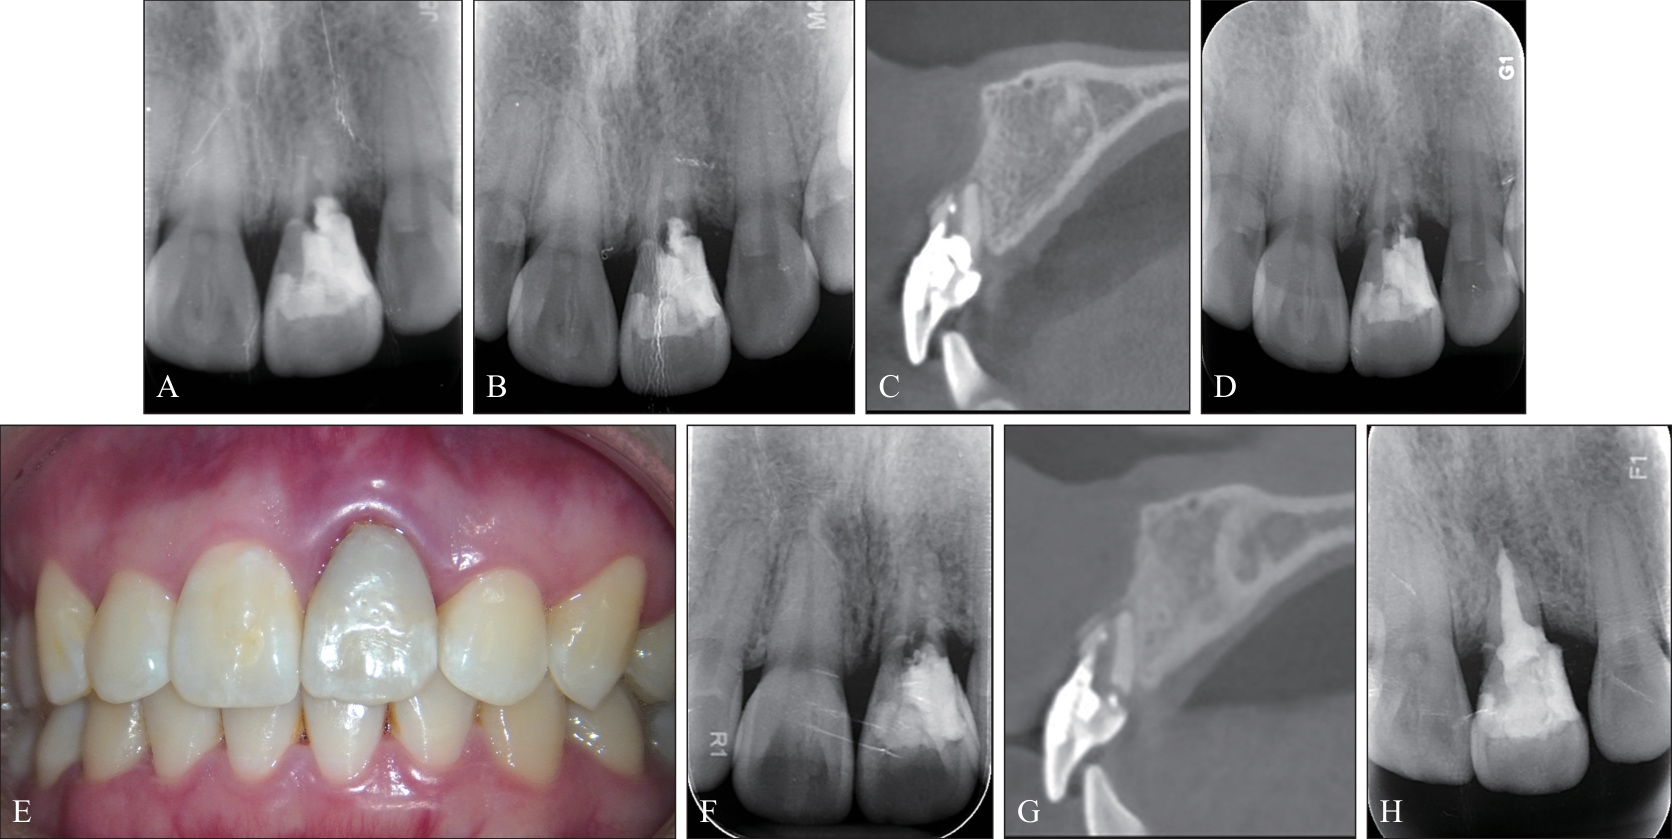

Patel S, Foschi F, Mannocci F, et al. External cervical resorption: a three-dimensional classification[J]. Int Endod J, 2018, 51(2): 206-214

Patel S, Krastl G, Weiger R, et al. ESE position statement on root resorption[J]. Int Endod J, 2023, 56(7): 792-801.

Patel S, Foschi F, Condon R, et al. External cervical resorption: part 2—management[J]. Int Endod J, 2018, 51(11): 1224-1238.

Patel S, Saberi N, Pimental T, et al. Present status and future directions: root resorption[J]. Int Endod J, 2022, 55(S4): 892-921.